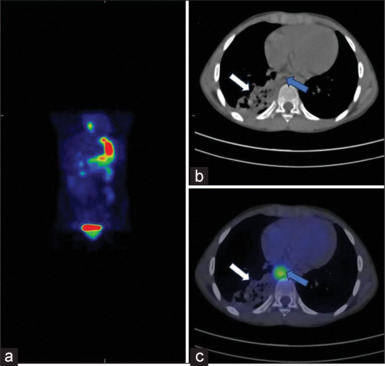

Enteric duplications are rare congenital anomalies, which can have varying presentations depending on the size, location, and type of mucosa present. Meckel scan, using technetium-99m pertechnetate (Tc-99m pertechnetate), is a useful modality for the detection of ectopic functioning gastric mucosa. Thoracic duplication cysts present as the initial photopenic area which is getting filled by Tc-99m pertechnetate in the delayed static images of Meckel scan. We report a rare case of foregut duplication cyst, where foregut duplication cyst is visualized earlier in Meckel scan.